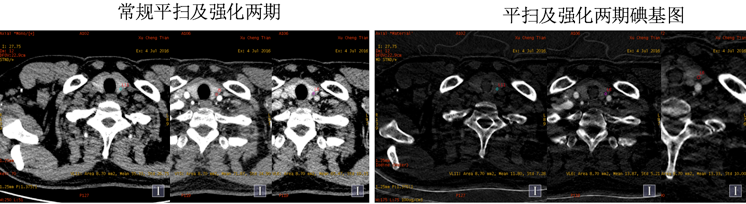

常规图像及碘基图显示病灶轻度强化。 能谱曲线:

右肺、上腔静脉及纵隔淋巴结病灶曲线斜率基本一致,而左甲状腺病灶能谱曲线与其明显不一致,综合CT平扫及强化各期特点以及病理结果,上腔静脉病灶考虑癌栓;左甲状腺病灶考虑甲状腺腺瘤(非转移病灶)可能大。 小结: